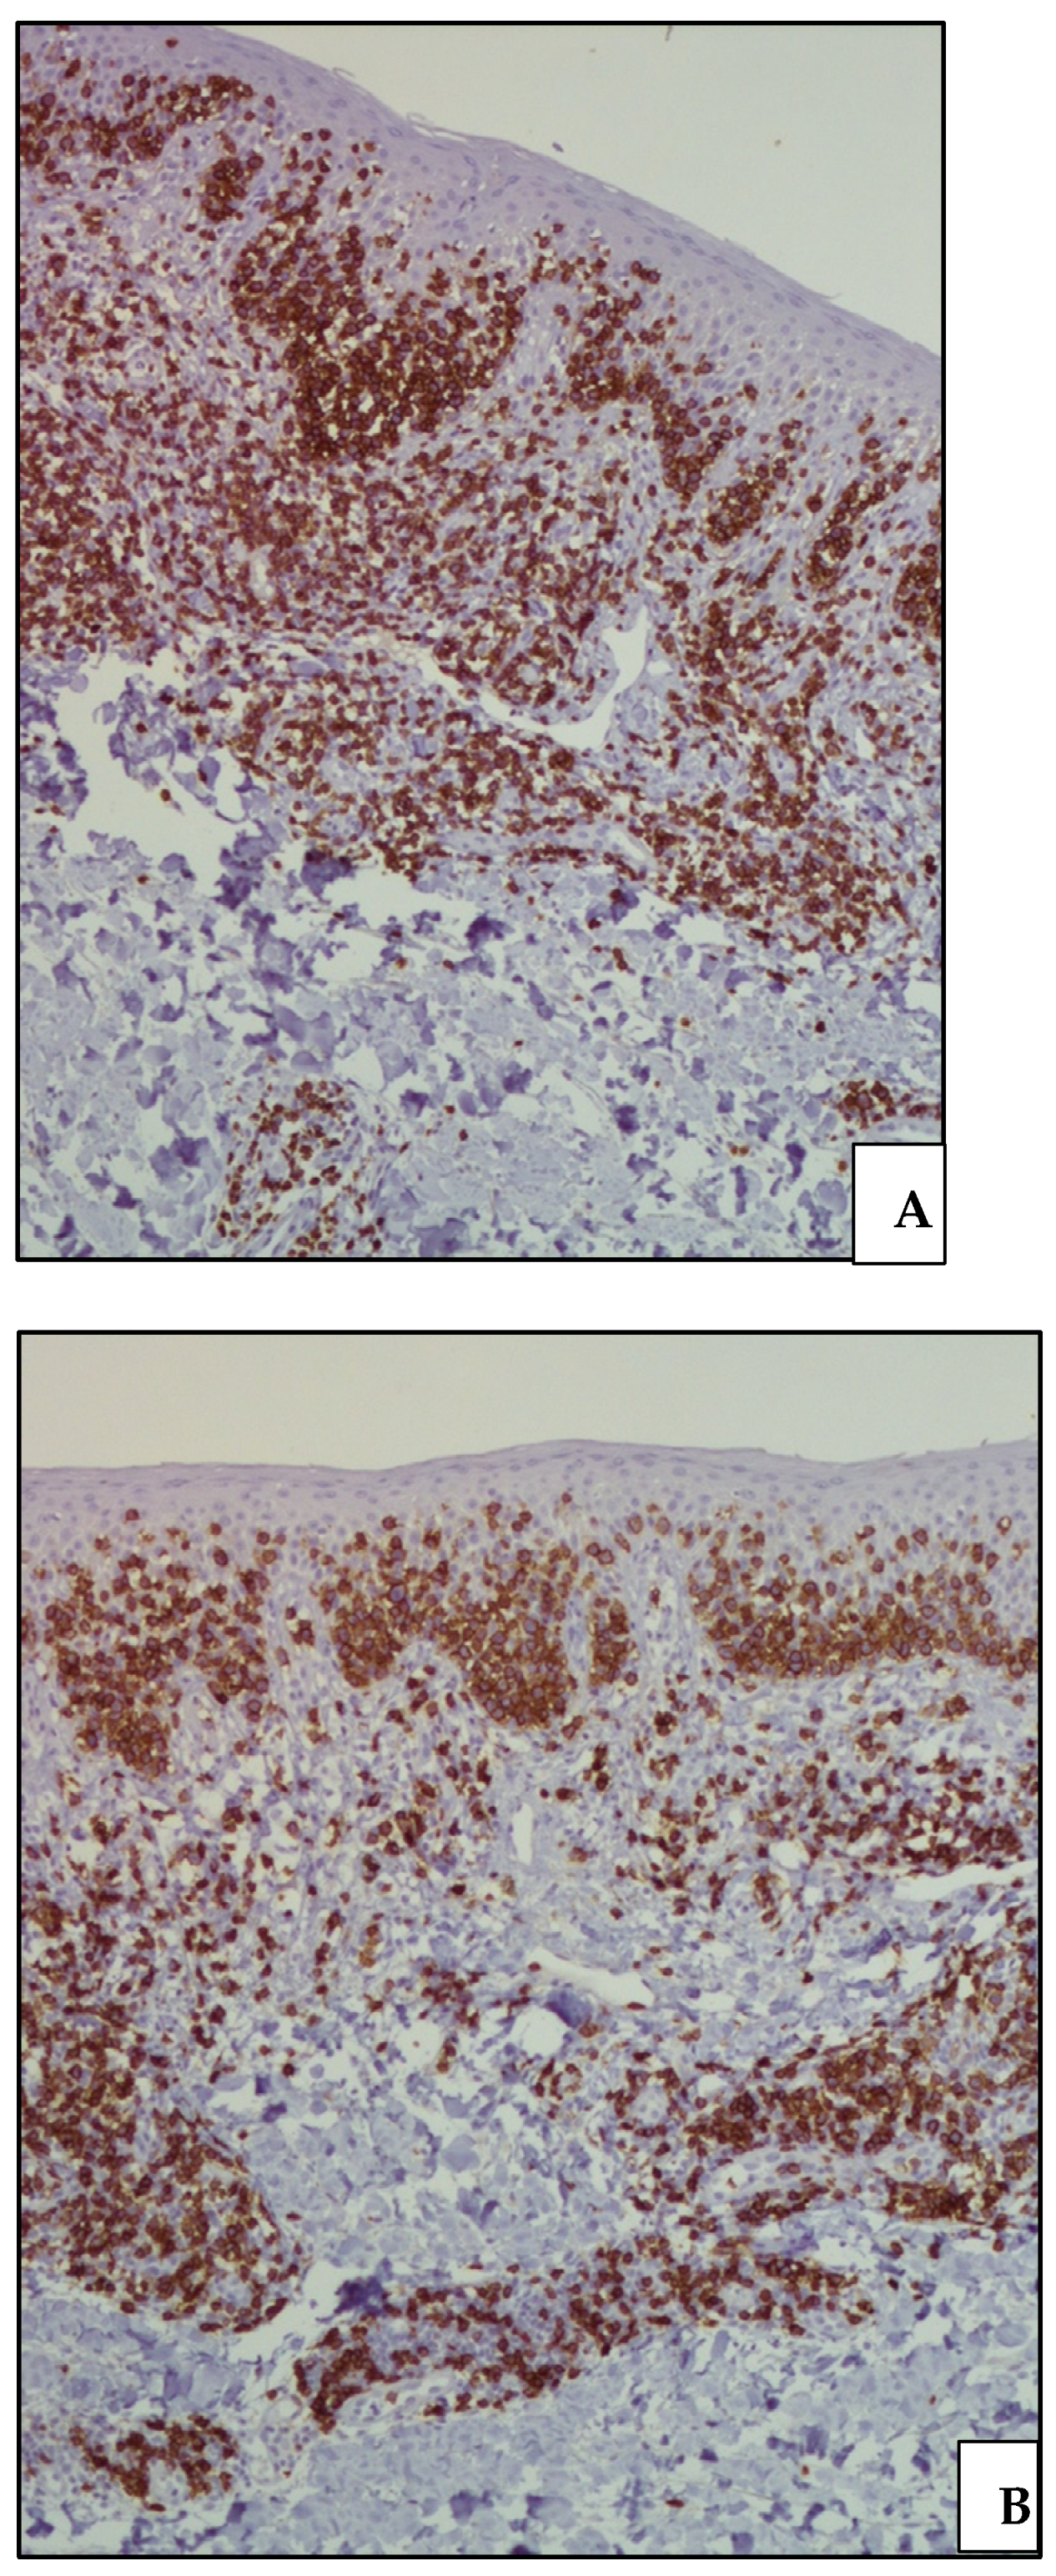

2. Case Presentation